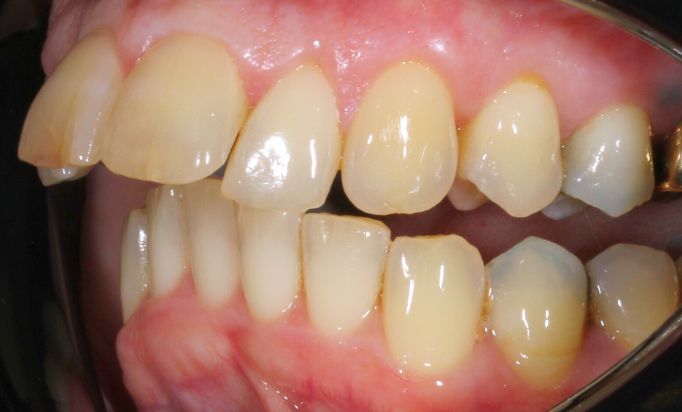

Cosmetic Dentistry

Improving smiles naturally

Helping you prevent dental issues with regular check-ups.